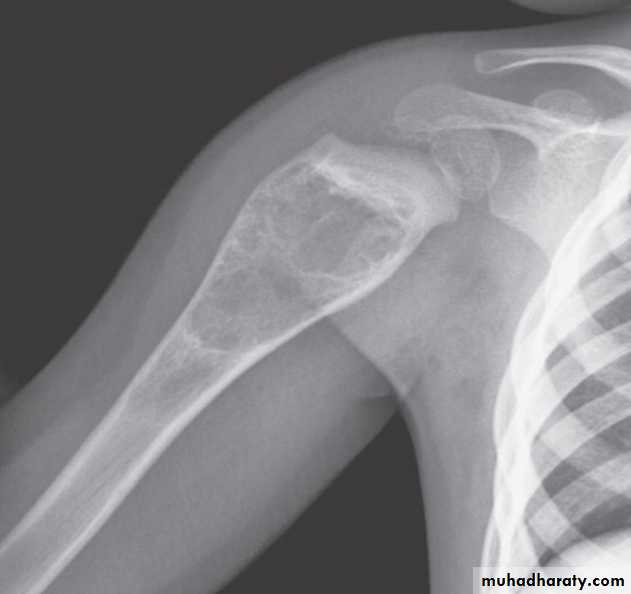

Area of bone destruction or sclerosis with ill-defined margins, wide zone of transition & periosteal reaction with or without cortical destruction & soft tissue swelling.Osteosarcoma :

Age: 5-20-yrs, elderly with Paget's disease.Site: metaphyseal around the knee joint.

Findings:

Lytic

Blastic

Mixed

Poorly defined bony destruction.

Sun ray speculation (periosteal reaction).

Elevation of the periosteum at the margin producing the so called Codman's triangle.

Cortical destruction.

Soft tissue swelling.